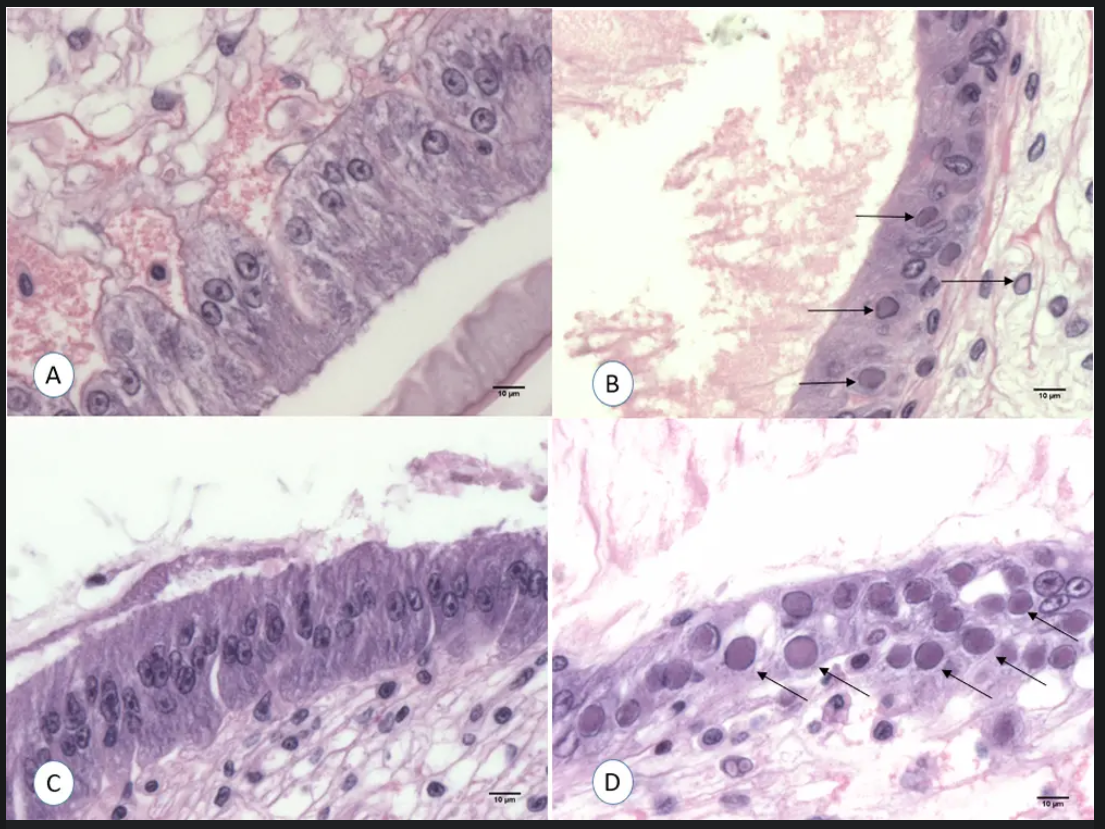

Mô tôm nhiễm WSSV sử dụng gây nhiễm đã gây tỷ lệ chết cao. Nhóm đầu tiên bắt đầu chết từ ngày thứ 2 sau gây nhiễm. Đến ngày thứ 4, khi tỷ lệ chết đạt 50%, số còn lại được thu hoạch. Kết quả PCR và nhuộm H&E xác nhận dương tính WSSV.

Phân tích mô học cho thấy thể vùi nội nhân đặc trưng của WSSV chỉ xuất hiện ở nhóm đối chứng dương. Các nhóm luộc từ 1 đến 30 phút không xuất hiện tổn thương mô học đặc trưng của WSSV.

Thí nghiệm gây nhiễm xác nhận rằng chỉ nhóm đối chứng dương (0 phút) gây chết và nhiễm WSSV. Các nhóm luộc từ 1–30 phút có tỷ lệ sống cao và không xuất hiện tổn thương mô học.